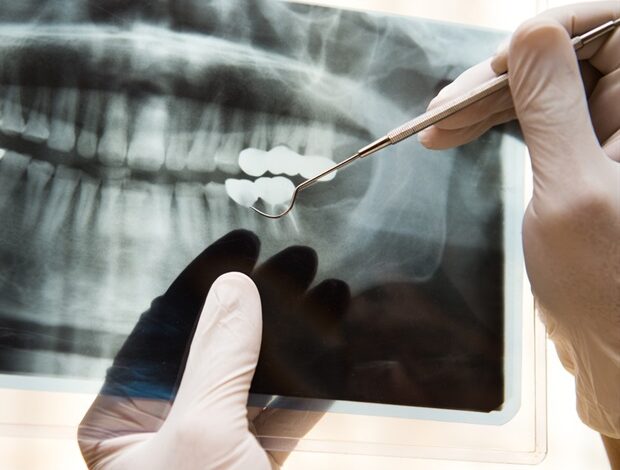

Modely hlubokého učení využívající rentgen hrudníku zaznamenaly v posledních letech pozoruhodný pokrok a vyvinuly se tak, aby splnily úkoly, které jsou pro člověka náročné, jako je odhad srdeční a respirační funkce.

Umělá inteligence je však jen tak dobrá, jak dobré jsou obrázky, které jsou do nich vloženy. Přestože rentgenové snímky pořízené v nemocnicích jsou před vložením do modelu hlubokého učení označeny informacemi, jako je místo a metoda snímkování, většinou se to provádí ručně, což znamená, že zejména v rušných nemocnicích dochází k chybám, chybějícím datům a nesrovnalostem.

To je dále komplikováno obrázky s různými rotacemi. Rentgenový snímek může být pořízen od přední k zadní části nebo naopak a může být také laterální, převrácený nebo otočený, což dále komplikuje soubor dat.

Ve velkých obrazových archivech tyto drobné chyby rychle přidají stovky nebo tisíce chybně označených výsledků.

Výzkumný tým na Lékařské fakultě univerzity v Ósace Metropolitan University, včetně postgraduálního studenta Yasuhita Mitsuyamy a profesora Daiju Uedy, si kladl za cíl zlepšit detekci chybně označených dat automatickou identifikací chyb dříve, než ovlivní vstupní data pro modely hlubokého učení.

Skupina vyvinula dva modely: Xp-Bodypart-Checker, který klasifikuje rentgenové snímky v závislosti na části těla; a CXp-Projection-Rotation-Checker, který detekuje projekci a rotaci rentgenových snímků hrudníku.

Xp‑Bodypart‑Checker dosáhl přesnosti 98,5 % a CXp‑Projection‑Rotation‑Checker dosáhl přesnosti 98,5 % pro projekci a 99,3 % pro rotaci. Výzkumníci jsou optimističtí, že integrace obou do jediného modelu by přinesla výkon, který změní hru v klinickém prostředí.

Přestože výsledky byly vynikající, tým doufá, že metodu dále vyladí pro klinické použití.

Plánujeme přeškolit model na rentgenových snímcích, které byly označeny, přestože byly správně označeny, i na těch, které nebyly označeny, ale ve skutečnosti byly označeny nesprávně, abychom dosáhli ještě větší přesnosti.“